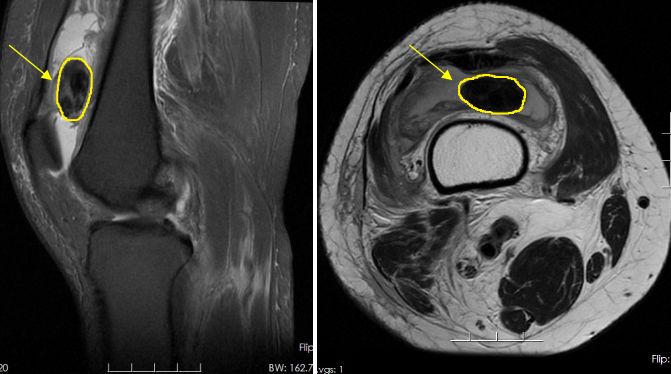

▲术前3.0核磁共振

为明确病因,柴亚胜为张阿姨安排了膝关节彩超及磁共振检查。膝关节平扫结果显示患者右膝周围软组织出现弥漫性异常信号;右膝关节髌骨上方有陈旧性积液和积血。

经过仔细研究分析后,柴亚胜认为患者右膝关节存在滑膜肿块、且有占位性病变,初步排除肿瘤的可能,考虑是“关节鼠”。